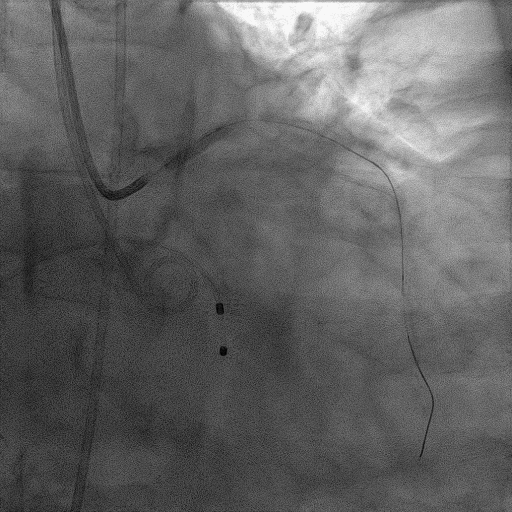

CAG:LAD近中段弥漫钙化,近段80%狭窄,中段90%狭窄,D190%狭窄,中间支近段90%狭窄,右冠近中段弥漫病变,最重狭窄50%。考虑患者胸痛症状可能为冠心病+AS共同作用,以及患者冠脉病变钙化严重,予以旋磨+PCI+TAVR一站式处理。

于中间支植入2.5*18mm支架

1.5mm旋磨头以16万RPM旋磨三次

3.0*15mm球囊后扩张

3.0*15mm球囊预处理LAD近段病变

复查冠脉造影结果满意

造影提示微少量返流,压力监测提示主动脉瓣压差7mmHg